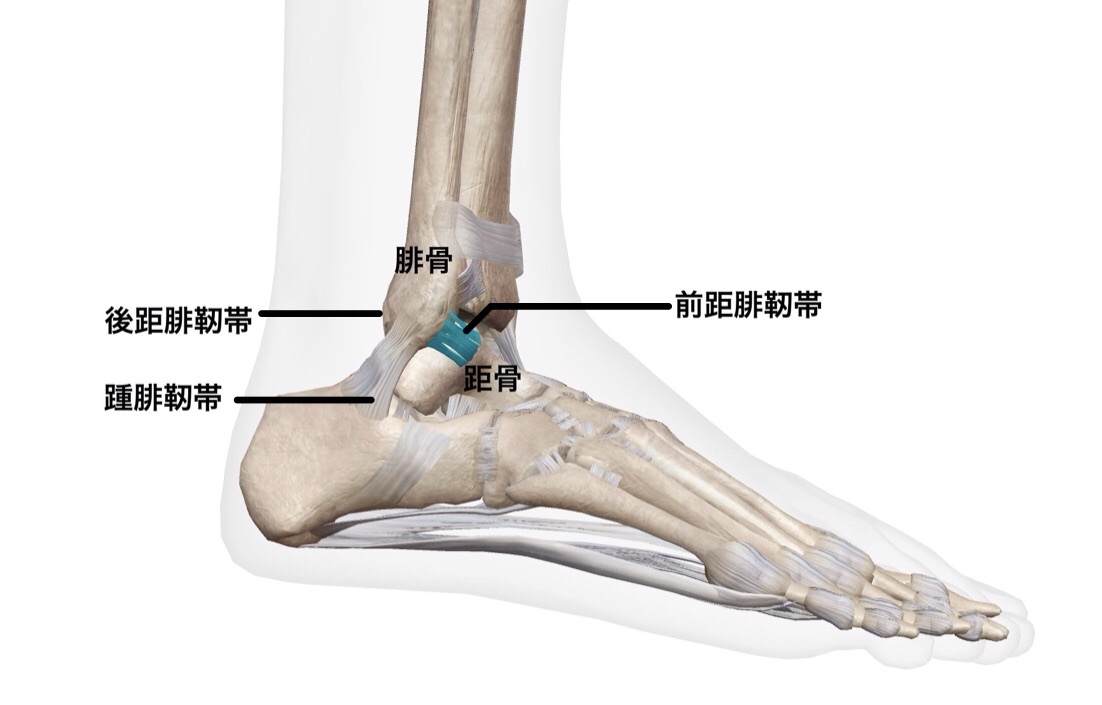

まず、足関節外側靭帯は3つの靭帯で構成されています。

それぞれの厚さは

・前距腓靭帯:約2mm

・踵腓靭帯:約6mm

・後距腓靭帯:約6mm

となっており、3つの靭帯の中で最も薄い靭帯です。